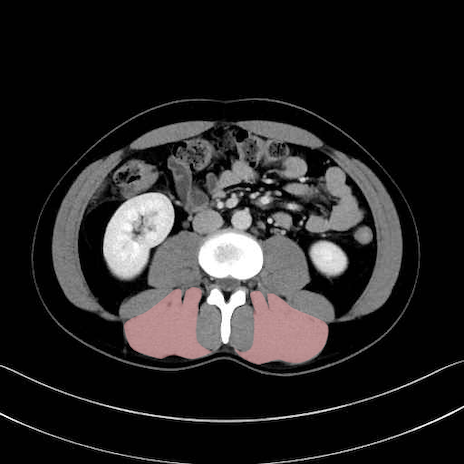

脊柱起立筋(erector spinae)のCT画像の解剖

脊柱起立筋 (Erector spinae)

多裂筋 (Multifidus)